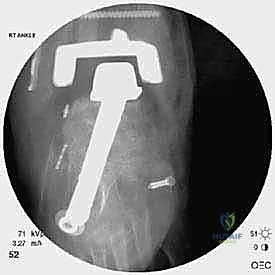

* دمج الكاحل (Ankle Arthrodesis): إذا كان التآكل العظمي هائلاً ولا يسمح بتركيب مفصل جديد، يتم إزالة المفصل الصناعي ودمج عظمة الساق مع عظمة الكاحل باستخدام مسامير وصفائح معدنية وطعوم عظمية.

علاج هذه الكسور يتطلب مهارة فائقة من الدكتور محمد هطيف، حيث يتم استخدام تقنيات الجراحة الميكروسكوبية وتثبيت الكسور باستخدام صفائح معدنية دقيقة ومسامير (Locking Plates) دون المساس بثبات المفصل الصناعي، أو يتم دمج علاج الكسر ضمن عملية مراجعة المفصل الكلية إذا كان المفصل نفسه تالفاً.

الخطوة الخامسة: تركيب المفصل الجديد أو الدمج

يتم إدخال المفصل الجديد المخصص للمراجعة، والذي يحتوي غالباً على سيقان (Stems) تدخل عميقاً في عظمة الساق وعظمة الكاحل لضمان الثبات الميكانيكي. في حال وجود كسور في الكعب، يتم تثبيتها في هذه المرحلة.